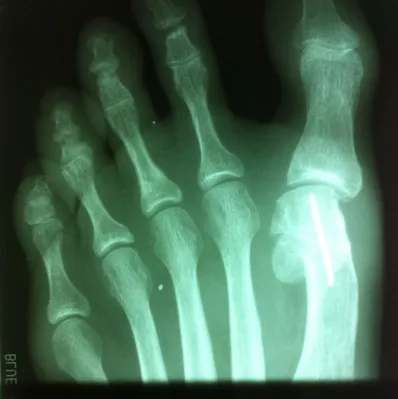

Varus position great toe after bunion surgery, the great toe is deviated laterally away from the lesser toes (left). Surgical procedure performed involved soft tissue correction and temporary fixation with a Kirschner wire (center). Several weeks after surgery the wire is removed and the great toe is now in rectus (straight) position.